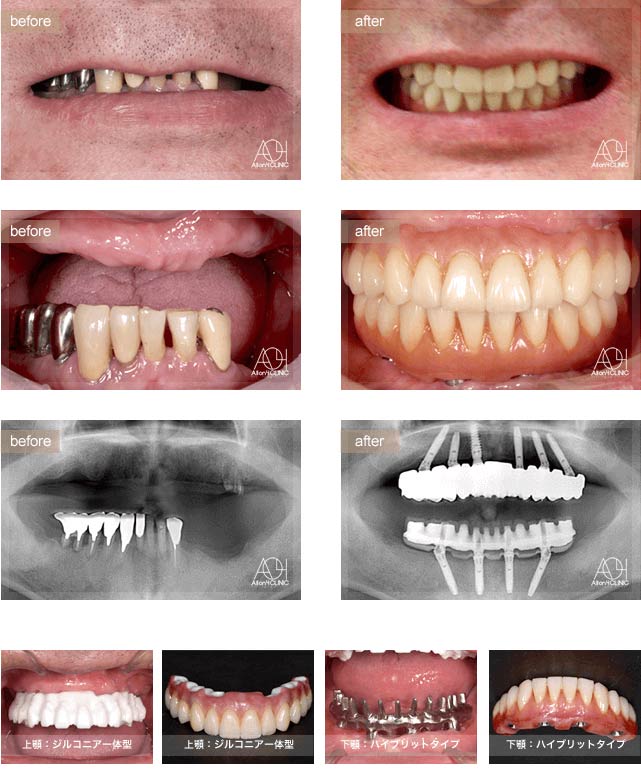

Treatment : All-on-4

- Upper All-on-4

- Lower All-on-4

Age : 62 Sex : 女 Y.M

| 主訴 | 入れ歯が合わなく痛いし、入れ歯を入れている事が嫌になってしまった。 |

| 治療内容 | X-guide(エックスガイドナビゲーションシステム)を用いてインプラントを正確に埋入。 上下オールオン4。 |

| 治療費(総額) | ¥7,200,000(税抜)『モニター割引適用』 |

| リスク | 治療後の口腔管理が不適切な場合、埋入したインプラント周囲に感染・炎症を起こし、脱落する可能性がございます。 |